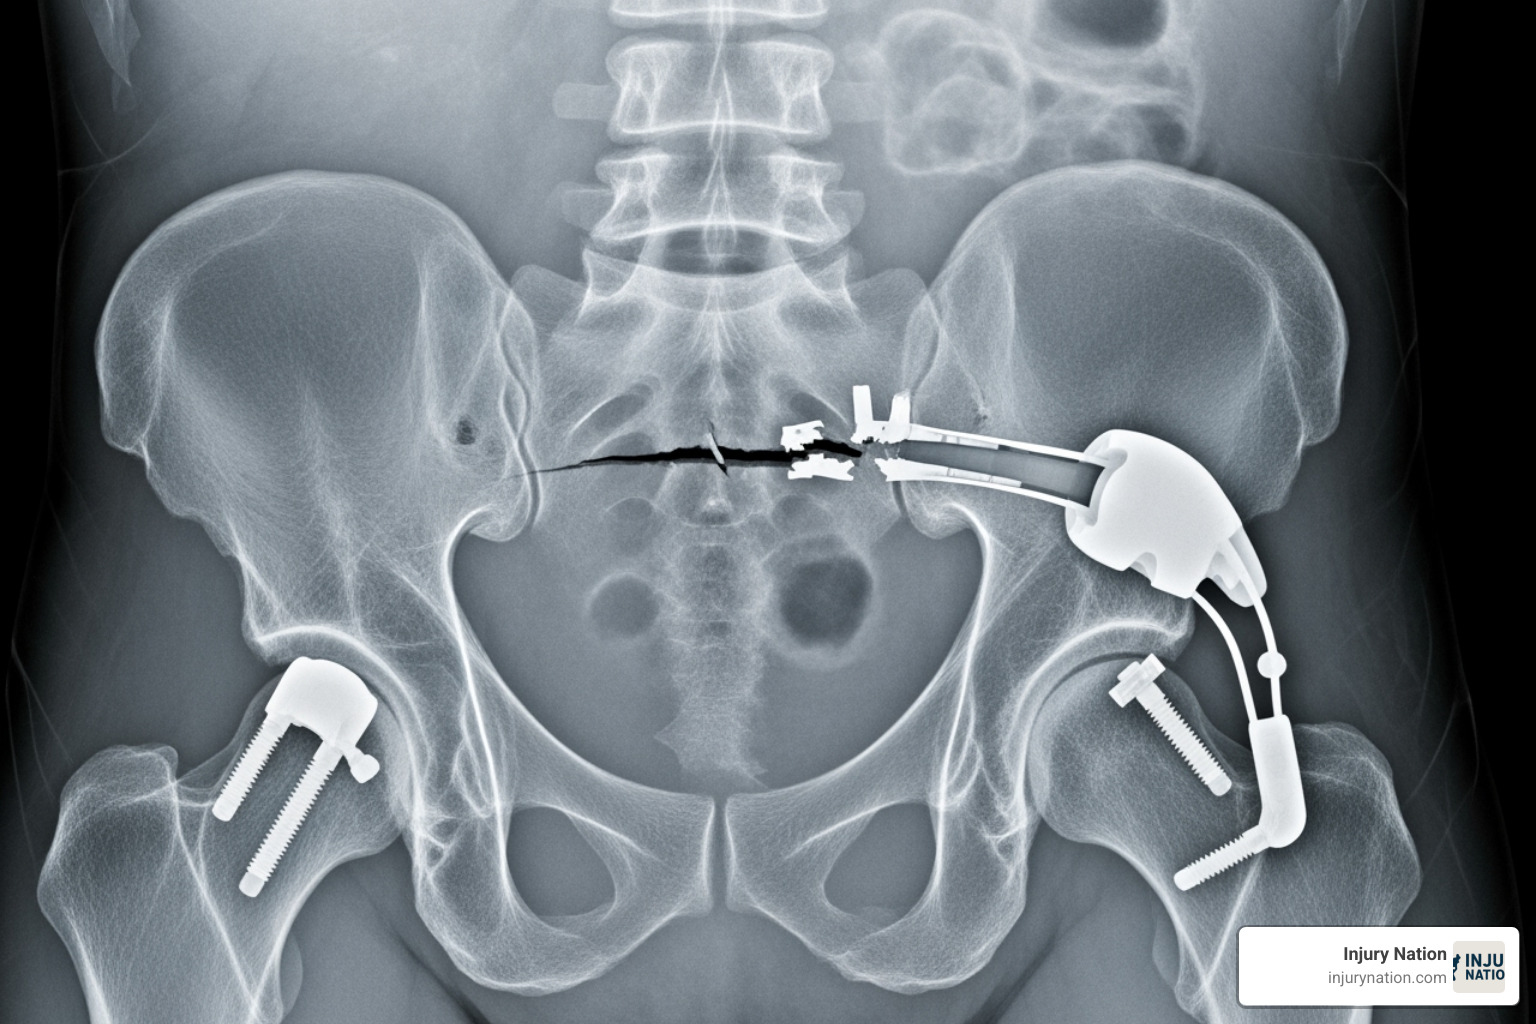

Design defects mean the device is inherently dangerous due to its fundamental design. Even with perfect manufacturing, the product is unsafe for its intended use. An example is a hip implant made from metals that corrode and release toxins.

- Hip and knee replacements (DePuy, Exactech) that fail prematurely, loosen, or cause metallosis (metal poisoning).

Common health consequences include chronic pain, persistent infections, and the need for painful revision surgeries to remove or replace a failed device. In some cases, devices can break apart or corrode, causing organ damage. The most tragic outcome is wrongful death. High-profile examples include metal-on-metal hip implants causing metallosis and pelvic mesh devices eroding through tissue, causing debilitating pain.